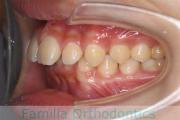

No.22V-449

- 主な症状:

- 上顎前突

- その他の症状:

- 叢生

- 年齢:

- 14歳

- 性別:

- 男性

- 抜歯部位

- 上:

- 44

- 下:

- 8448

- 主な使用装置:

- FEA

- 治療にかかった費用:

- 87万円

歯並びをきれいにしたいということで来院されました。上下左右から小臼歯を抜歯して、マルチブラケット法を行っています。2年弱、25回程度の通院が必要でした。

かなり強い叢生(でこぼこ、凹凸、ガタガタ)ですので、保定をしっかりしないと後戻りのリスクがあります。

- ≫治療後

-

上顎

下顎

前歯の関係など

右側

正面

左側